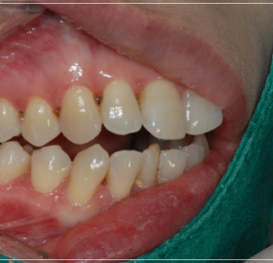

이 처럼 입을 다물어도 어금니만

맞물린 채 앞니가 맞물리지 않는 증상을

개방교합이라고 부르는데요.

개방교합은 입을 다물때 안쪽

어금니만 맞닿고 앞니 쪽은 닿지 않아

입술이 붕 떠 있는 상태를 말했어요.

이처럼 앞니가맞물리지 않고

붕 떠있는 증상이 오랜기간 지속되면

점차 얼굴 안면 골격의 부정적인

변화를 발생시키기도 하기 때문에